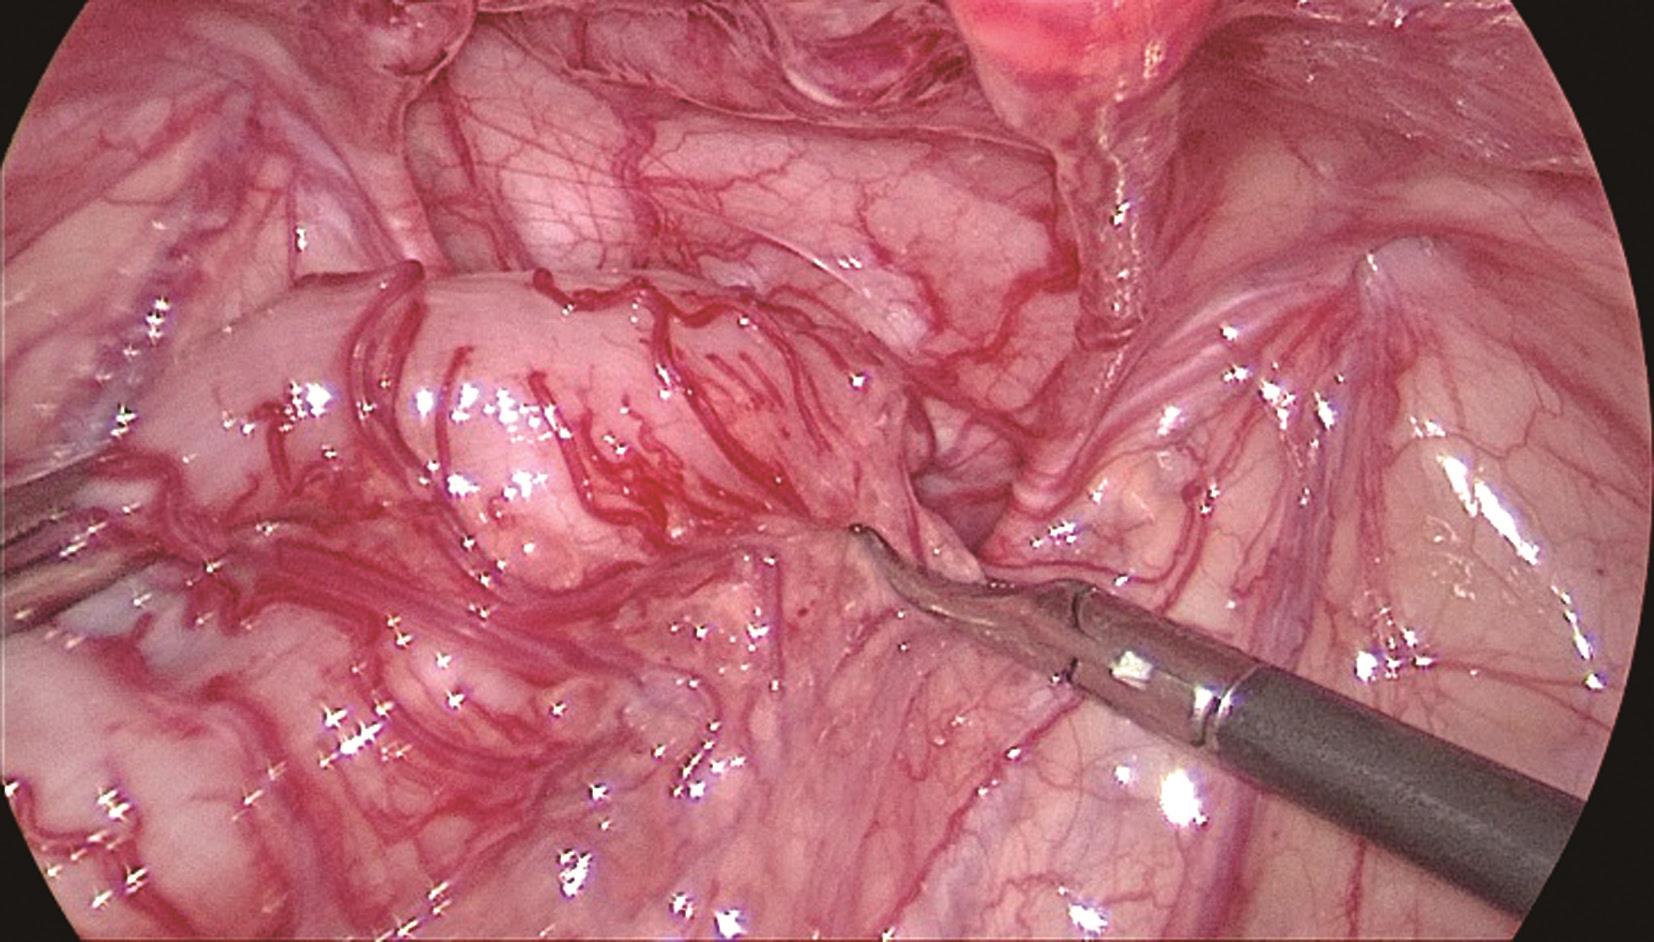

图3-22 腹腔镜显示乙状结肠

乙状结肠肠管扩张,肠壁浆肌层增厚,颜色苍白。